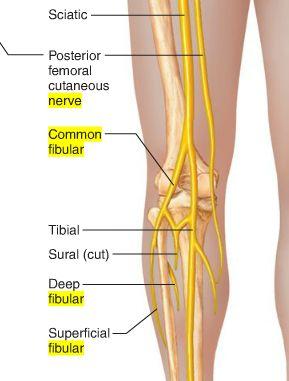

Into which two nerves does the sciatic nerve bifurcate?

tibial and common fibular

The common fibular nerve is formed from ventral rami from spinal cord levels _______

L4 - S2

The common fibular nerve is the (lateral/medial) division of the sciatic nerve

lateral

Describe the pathway of the common fibular nerve

wraps around the neck of the fibula

bifurcates into deep and superficial fibular nerves

What muscle does the common fibular division of sciatic nerve innervate?

ONLY biceps femoris short head

To which nerve might there be damage if a patient is suffering from foot drop?

common fibular nerve

What would be the consequences if the common fibular nerve was completely severed?

Patient would be unable to evert foot

numbness on dorsum of foot

unable to doriflex or extend digits of foot

The superficial fibular nerve is the (lateral/medial) branch of the ________

lateral; common fibular nerve

which muscles does the superficial fibular nerve innervate?

both lateral leg muscles (fibularis longus and fibularis brevis)

The deep fibular nerve is the (medial/lateral) division of the _________-

medial; common fibular nerve

What is the path of the deep fibular nerve?

travels between tibialis anterior and extensor hallucis longus

continues onto the dorsum of the foot for sensory innervation in the flip flop area

What is the pathway of the superficial fibular nerve?

runs between fibularis longus and fibularis brevis

continues onto the dorsum of the foot

Which muscles does the deep fibular nerve innervate?

innervates all anterior leg muscles (extensor hallucis longus, extensor digitorum longus, tibialis anterior, and fibularis tertius) and both muscles of the dorsum of the foot (extensor digitorum brevis, extensor hallucis brevis)

O C D of common fibular nerve

O sciatic nerve

C forms as sciatic nerve bifurcates at apex of popliteal fossa. follows medial border of biceps femoris with its tendon. passes over posterior aspect of head of fibula then winds around neck of fibula deep into fibularis longus where it divides into deep and superficial fibular nerves

D knee joint via articular branch and lateral aspect of posterior leg via sural cutaneous nerve

(common fibular branch of sciatic nerve innervates short head of biceps femoris)

OCD of superficial fibular nerve

O common fibular nerve

C arises between fibularis longus and neck of fibula. descends into lateral compartment of leg; pierces deep fascia at distal third of leg to become subcutaneous

D fibularis longus and brevis. medial dorsal cutaneous n, intermediate dorsal cutaneous n

OCD of deep fibular nerve

O common fibular nerve

C arises between fibularis longus and neck of fibula; passes through extensor digitorum longus and descends on interosseous membrane. crosses distal end of tibia and enters dorsum of foot.

D tibialis anterior, extensors digitorum brevis and longus, extensor hallucis brevis and longus, and fibularis tertius. lateral cutaneous of big toes, medial cutaneous of second toe.